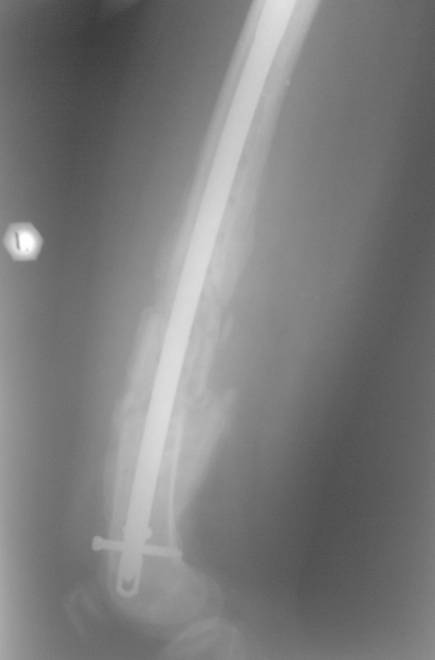

В мае 2007 года оперирована в Уральском НИИТО г. Екатеринбурга. Выполнено: полузакрытое удаление пластины и винтов, IM блокируемый остеосинтез.

На сегодняшний момент (2 месяца после операции). Больная передвигается при помощи трости из-за чувства неуверенности и ощущения онемения в подколенной ямке. В квартире передвигается без дополнительной опоры. Снимки в аттаче.